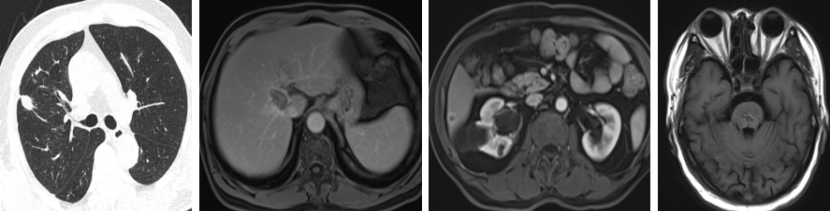

2022.3.29 复查:

1. 右肺上叶近水平裂实性结节,较前增大;

2. 右肺多发结节,部分较前略增大;

3. 肝右叶S8段异常强化灶,考虑转移性肿瘤,较前相仿;

4. 肝SVI段新发结节,考虑转移瘤;

5. 脑干转移瘤并周围水肿,较前增大。

2022.4.2 始行TAS-102+贝伐珠单抗(双周方案)治疗8个周期,6周期时复查,疗效评价为缩小的SD。